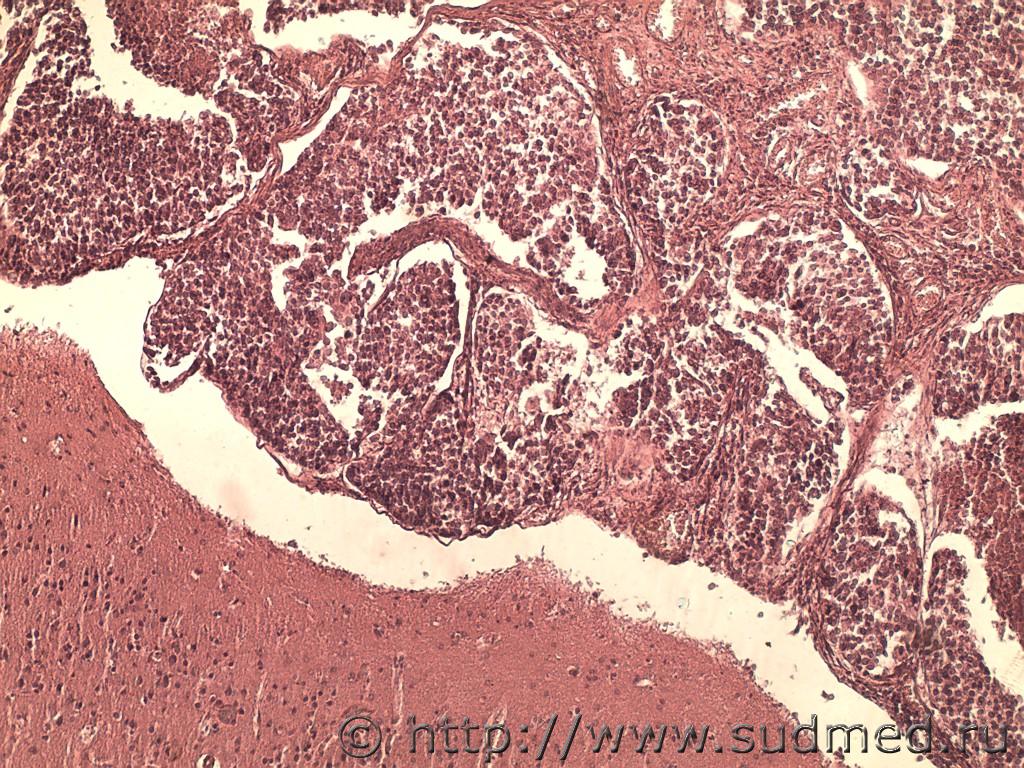

Уважаемы коллеги! У меня женщина 1977 г.р на вскрытии в области малого таза обширные спайки, клетчатка замещена патологической тканью хрящевой плотности, дифференцировать внутренние половые органы было невозможно; метастазы в ММО полушарий, мозжечка, спинного мозга, костях. Со слов родственников при жизни диагностирован рак половых органов (то ли яичников, то ли матки- внятно не могут ответить), долгая химиотерапия. У меня микропрепараты клетчатки малого таза, ММО структур ГМ и СМ, позвоночник с раком (полагаю, метастазы). Скажите, возможно ли дифференцировать название опухоли по метастазам, как вы пишете в таком случае диагноз? Не хочу промахнуться, иначе потом родственники найдут дома документы с названием рака и не дай бог это не совпадёт с моим диагнозом, будут разборки. Заранее спасибо

Согласен! Мелкоклеточная (метастатическая) карцинома не уточненного генеза( это м.б.что угодно и их видов очень много)